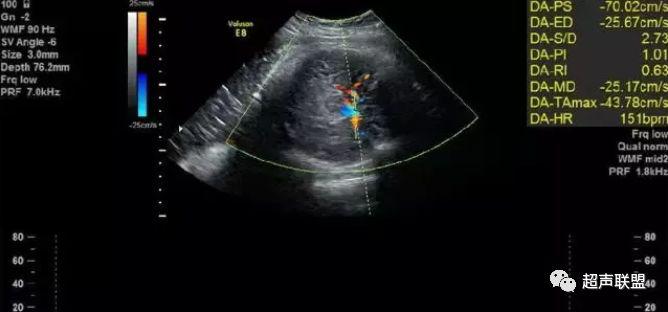

3 胎儿静脉导管

当右心负荷增大,心功能失代偿时,静脉回流受阻,静脉导管a波收缩期流速下降,血流消失甚至倒置。

5、静脉导管:a波消失或反向(见于严重的胎儿宫内缺氧);

3、静脉导管a波反向或消失;

图5 胎儿宫内正常静脉导管

图6 胎儿宫内缺氧时静脉导管a波反向